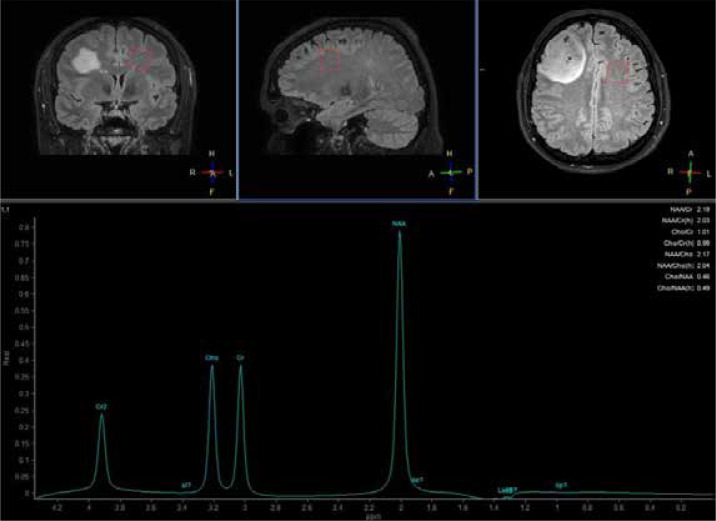

胶质母细胞瘤是成人恶性原发性脑肿瘤中最常见、最具侵袭性的一种。标准治疗方法是手术切除,然后进行放疗和化疗。尽管采用了最佳治疗方法,但患者的预后仍然很差。术前确定胶质母细胞瘤的边缘仍然有利于彻底切除肿瘤。放疗对术后治疗至关重要,但放射抗药性是导致高死亡率的一个重大挑战。先进的成像技术可用于分析瘤周脑区(PTZ)的变化。因此,这些技术可能会开发出新的治疗方案,尤其是针对肿瘤边缘部位的治疗方案,从而改善胶质母细胞瘤患者的预后。胶质母细胞瘤的临床表现多种多样,主要取决于肿瘤的位置和大小。胶质母细胞瘤的特点是瘤内细胞异质性和向肿瘤周围正常组织的广泛、弥漫性浸润(称为 PTZ)。神经成像技术,如弥散加权成像(DWI)、弥散张量成像(DTI)、灌注加权成像(PWI)、质子磁共振波谱(1H MRS)和化学交换饱和转移(CEST)是评估肿瘤浸润和切除边缘的有用方法。

Glioblastomas are the most common and aggressive form of malignant primary brain tumors in adults. The standard treatment is surgical resection followed by radiotherapy and chemotherapy. Despite optimal treatment methods, the prognosis for patients remains poor. Preoperative determination of glioblastoma margins remains beneficial for the complete removal of the tumor mass. Radiotherapy is essential for post-surgery treatment, but radioresistance is a significant challenge contributing to high mortality rates. Advanced imaging technologies are used to analyze the changes in the peritumoral brain zone (PTZ). Consequently, they may lead to the development of novel therapeutic options, especially targeting the marginal parts of a tumor, which could improve the prognosis of glioblastoma patients. The clinical presentation of glioblastoma is heterogeneous and mostly depends on the location and size of a tumor. Glioblastomas are characterized by both intratumoral cellular heterogeneity and an extensive, diffuse infiltration into the normal tissue bordering a tumor called the PTZ. Neuroimaging techniques, such as diffusion-weighted imaging (DWI), diffusion tensor imaging (DTI), perfusion-weighted imaging (PWI), proton magnetic resonance spectroscopy (1H MRS), and chemical exchange saturation transfer (CEST) are useful methods in the evaluation of the tumor infiltration and thus the resection margin.